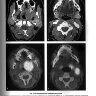

Примеры страниц из книги "Визуализация заболеваний шеи" - Труфанов Г. Е., Припорова Ю. Н.